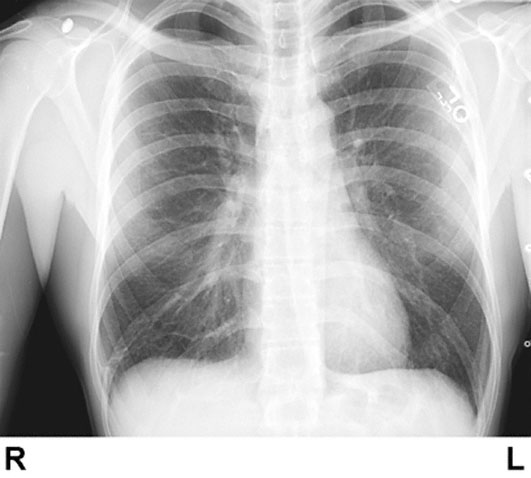

A 27-year-old man comes to the physician because of an 8-month history of shortness of breath with exertion. He has a 1-week history of mild shortness of breath after climbing one flight of stairs. He has not had fever, cough, or weight loss. He does not smoke. He is employed as an office worker. Vital signs are within normal limits. Jugular venous pressure is 7 cm H2O. There is clubbing of the fingers bilaterally. Crackles are heard throughout the lungs. Arterial blood gas analysis on room air shows:

An x-ray of the chest is shown. Pulmonary function tests show a normal FEV1:FVC ratio and decreased diffusion capacity of the lung for carbon monoxide. Which of the following is the most likely explanation for this patient’s dyspnea?